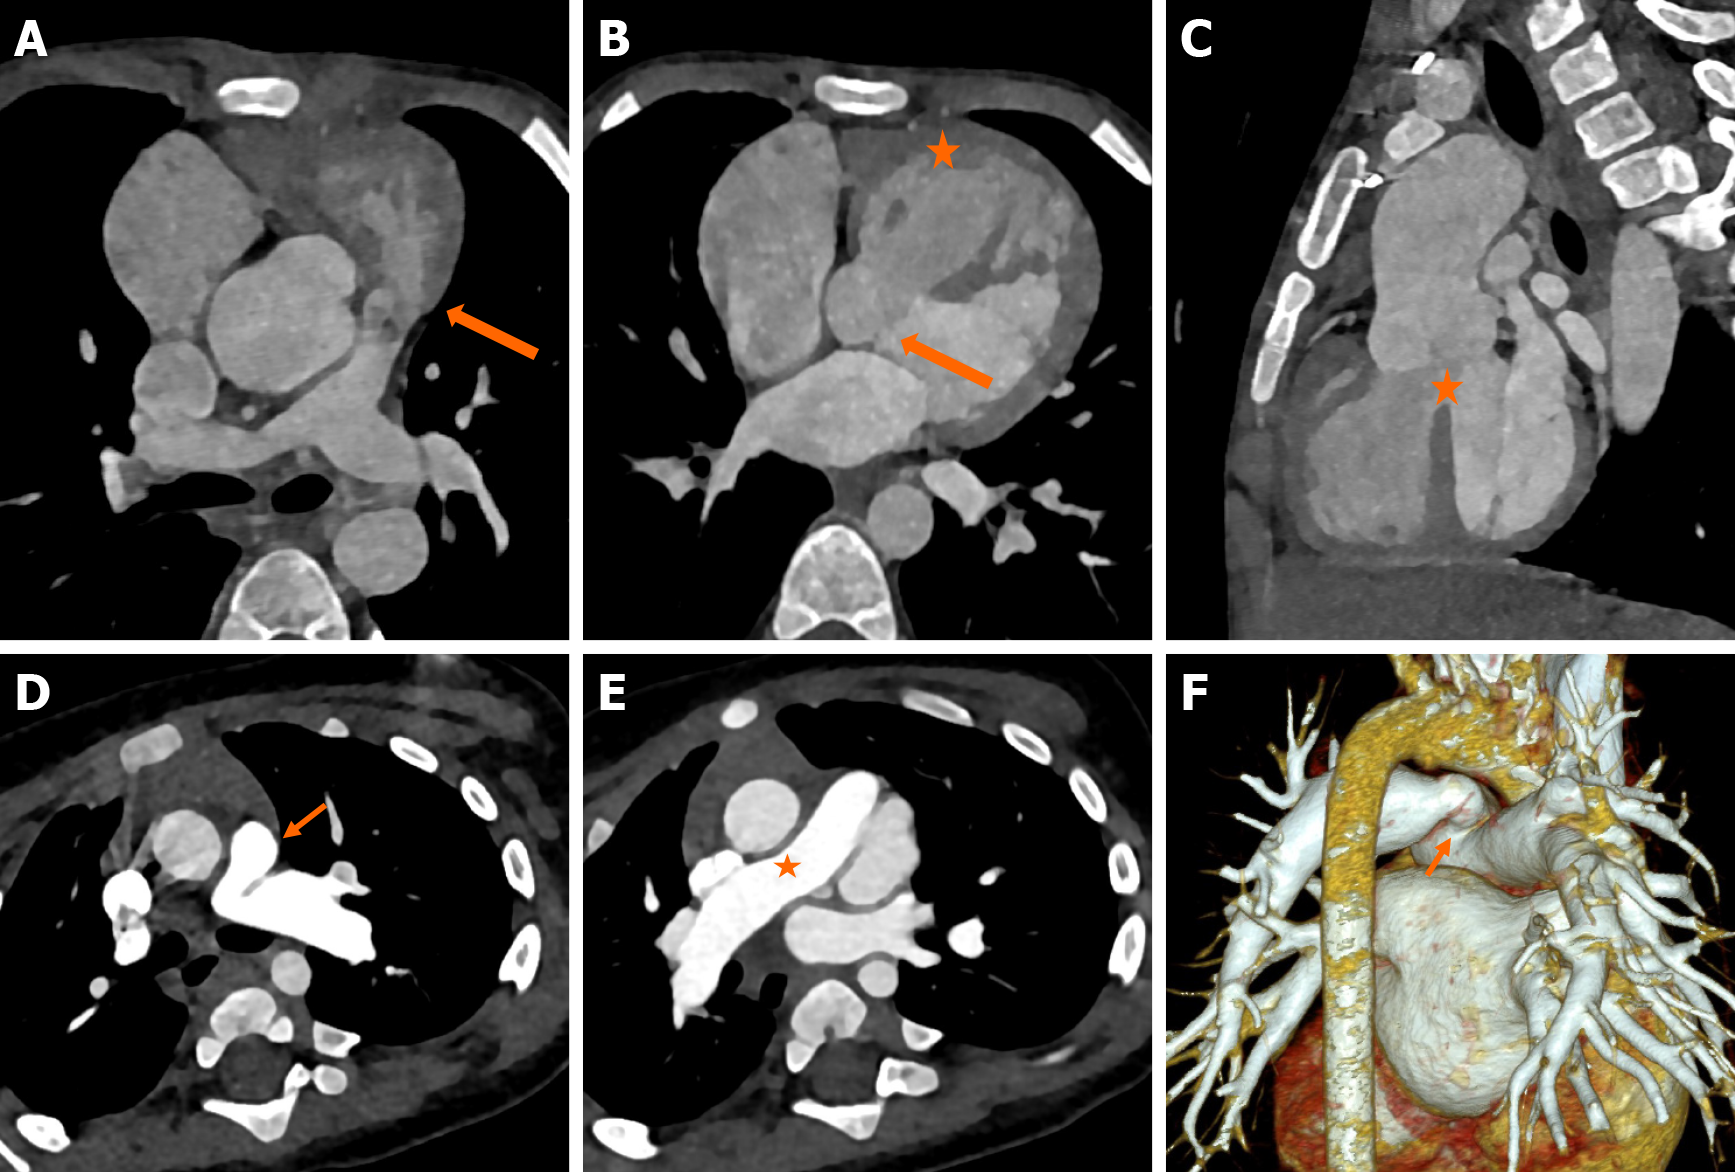

The classical components of TOF, including perimembranous VSD, aortic override, pulmonary stenosis/atresia, and consequent right RVH, are very well delineated on CT (Figure 5A-C). The aortic override in TOF is typically less than or equal to 50%, in TOF. The degree of RVOTO is variable. Pulmonary stenosis may be infundibular, valvular, or supravalvular. Isolated left PA stenosis is the most common (Figure 5D-F). Rarely, stenosis of the branch PA may be coexistent with main PA stenosis (Figure 6A-D)[37]. In cases with pulmonary atresia, the main PA is atretic, and the branch pulmonary arteries may be confluent or isolated (Figure 6E-G). The PV may be absent in 3%-6% cases and is characterized by an aneurysmal main PA (Figure 6H)[38].

Figure 5

Figure 5 Computed tomography images. A-C: Axial (A and B) and sagittal reformatted images (C) of computed tomography angiography in a child with cyanosis, showing infundibular pulmonary stenosis (block arrow in A), right ventricular hypertrophy (asterisk in B), perimembranous ventricular septal defect (block arrow in B) with 50% aortic override (asterisk in C) consistent with classical tetralogy of Fallot; D-F: Axial (D and E) images showing stenosis at the origin of the left pulmonary artery (arrow). The right pulmonary artery was normal (asterisk); F: Three-dimensional volume rendered image showing the left pulmonary artery stenosis (arrow).